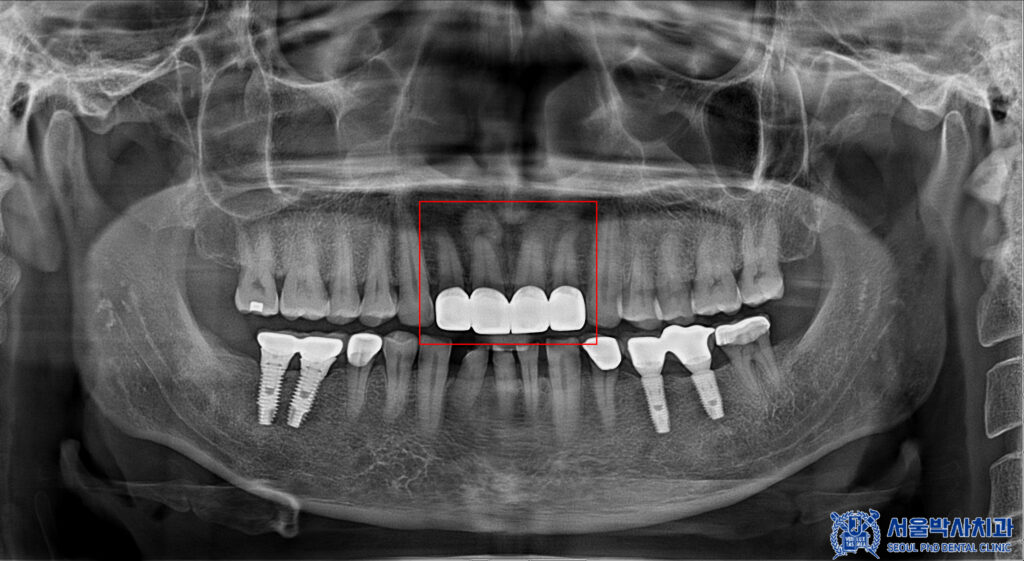

파노라마를 촬영하고

확인해 보았을 때도,

보철물이 방사선불투과성이라

치아 내부를 정밀하게

확인할 수 없었습니다.

그래서 산성동치과 서울박사치과에서는

해당 브릿지를 제거하여

내부 상황을 확인하기로

환자분과 상의 후 결정하였습니다.